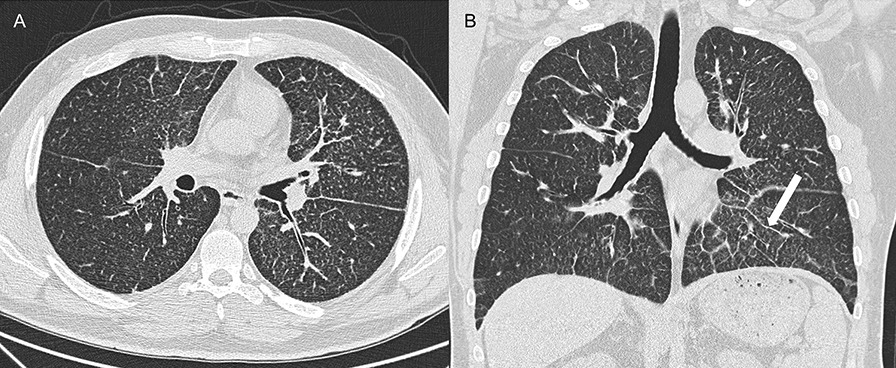

尽管佳学基因收集的肺泡微石症 (PAM)病例发生在不同年龄段,但大多数患者是在 10 至 30 岁之间诊断出来的。许多患者是偶然诊断出来的,这怀与家族性健康检查有关。呼吸困难、干咳、疲劳和胸痛是有症状患者的常见症状。气胸、杵状指、咯血、缺氧和发绀均也在病例中得到记录 。肺功能通常正常或呈限制性模式。PAM通常进展缓慢,但也可能观察到较轻或更具侵袭性的病程。通过X 射线进行胸透检查通常很明显,与临床严重程度不成比例。胸部 X 光检查通常显示与钙化相对应的沙粒状图案,以双侧基底区和中间区为好发区。高分辨率计算机断层扫描 (HRCT) 上可见整个肺部分布着大量粟粒状钙化结节(图 2)。X 线表现非常有特征性,对于具有典型 HRCT 表现的病例,无需进行肺活检即可确诊。

图 2.肺泡微结石症患者的HRCT示例